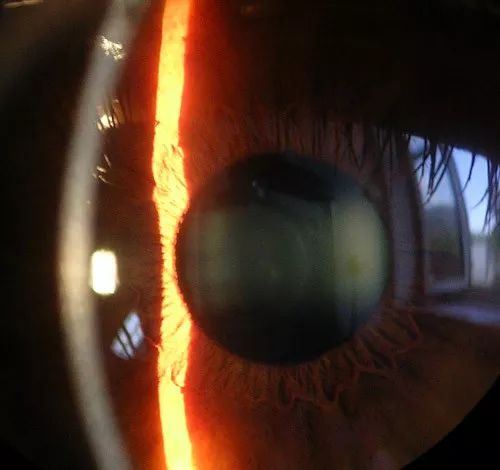

角膜是什么?

角膜,是眼球最前方的透明多层组织,

眼球的结构(cornea就是角膜)